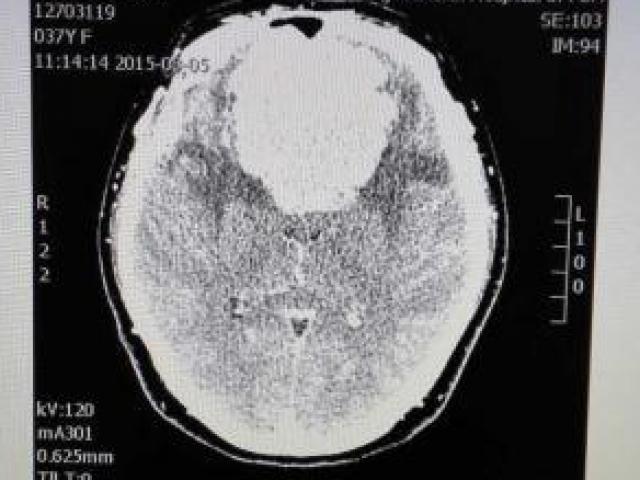

8h sáng ngày 21/12, bà Chài được đưa vào phòng phẫu thuật. Đúng 8h 30 phút, các bác sĩ gây mê hồi sức đã tiến hành đặt nội khí quản, công tác gây mê. Các bác sĩ đã vẽ phác họa để có thể cắt bỏ khối u tốt nhất. 11h trưa các bác sĩ bắt đầu rạch dao vào khối u. Ca phẫu thuật kéo dài đến 16h 30 phút mới hoàn tất. Bệnh nhân đã được đưa xuống phòng hậu phẫu.

Để có được ca mổ dài hơn 8 tiếng thành công, bác sĩ Hải cho biết về phía Bệnh viện Răng Hàm Mặt Trung ương, bệnh viện đã chuẩn bị hết sức chu đáo từ các kíp bác sỹ phẫu thuật hàm mặt, sọ não, gây mê... Các bác sĩ của Bệnh viện Việt Đức sang hỗ trợ.